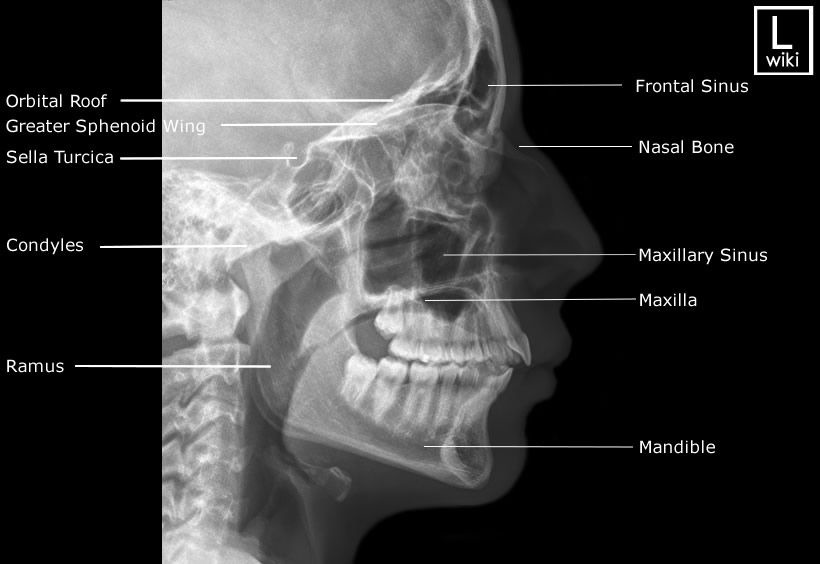

Lateral Facial Bones

Part Position: Head in true lateral; IPL perpendicular; IOML parallel to bottom of IR.

Central Ray: Perpendicular to zygoma (midway between outer canthus and EAM).

Collimation: 6×10 L/W